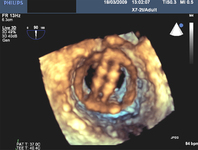

Prolapso do folheto P2 da valva mitral: visualização 3D

Do acervo de Prakash P. Punjabi